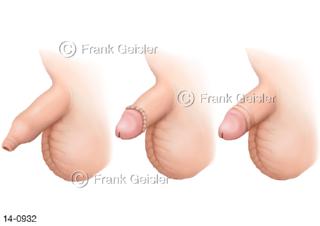

Bildergalerie Urogenitalsystem

Bilder zum Urogenitalsystem mit Urogenitalorgane, Urogenitaltrakt, zum Harn- und Geschlechtsapparat, Harnorgane und Geschlechtsorgane, Organe der Harnwege und der Fortpflanzung, Harnorgane und Geschlechtsorgane im männlichen und weiblichen Urogenitalsystem